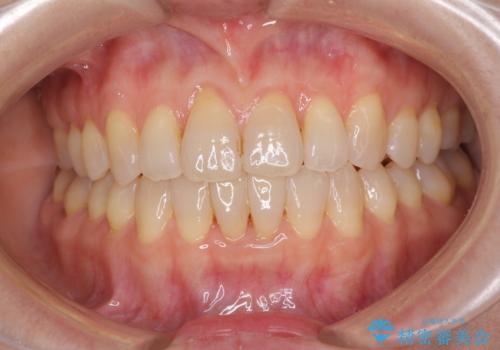

前歯の叢生と切端咬合 インビザラインによる矯正治療

- 前歯のデコボコを気にして来院された患者様です。

上下前歯の先端同士が接触する切端咬合であったため、上顎は歯列を拡大し、下顎はIPR(歯と歯の間を削る)により叢生を解消しながら歯列を小さくすることとしました。

矯正装置にはインビザラインを用いることとしました。

治療前から歯肉退縮が認められ、矯正治療により悪化する可能性が考えられたため、無理のない歯の移動と頻繁な経過観察を行いました。

切端咬合はスムーズに解消され、前歯の負担を軽減させることができました。